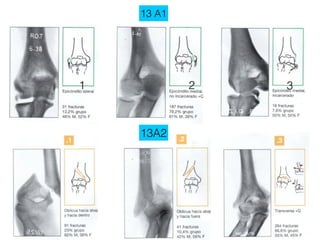

13 A1

1           2   3

13A2

13 A1 1 2 3 13A2